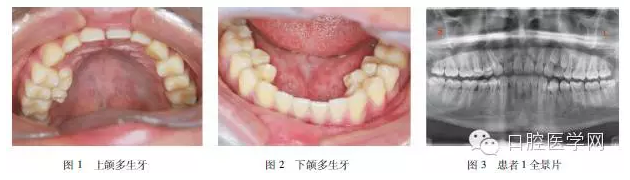

患者1,男,16歲,患者2年余前發(fā)現(xiàn)口內(nèi)長(zhǎng)出多顆多余牙齒。奶奶及父親均有多余牙拔除史,具體不詳,母親孕期無特殊接觸史。??茩z查:恒牙32顆完全萌出,545445舌側(cè)及34之間舌側(cè)各可見1顆多生牙,5舌側(cè)多生牙可見冠部齲損(上頜多生牙見圖1,下頜見圖2)。全景片(圖3)示患者前磨牙區(qū)多生牙共9顆,其中萌出7顆,左上頜2顆埋伏阻生,位于恒牙根旁。